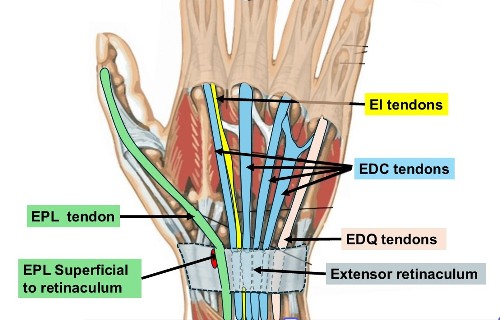

- The EPL = Extensor Pollicus Longus tendon runs along the back of the wrist to the thumb and wraps around Lister’s tubercle, using it as a pulley.

- The muscles are in the forearm. Tendons are like rope joining the muscles to the fingers and thumb. There is a strap of tissue ( extensor retinaculum) on the back of the wrist that holds the tendons down. There are 6 tunnels on the back of the wrist containing the Extensor tendons to the thumb, fingers & wrist.

- EPL Decompression - Removing the EPL from the groove adjacent to Lister’s tubercle & placing it superficial to the retinaculum

2. EI to EPL tendon transfer.

- There are 2 tendons that extend the Index finger ( EI & EDC tendons)

- The EI tendon is available for transfer because the EDC tendon to the index finger can still provide normal index finger extension on its own

- The Extensor Indicis (EI) tendon (used to extend the index finger) is redirected to take over the function of the EPL.